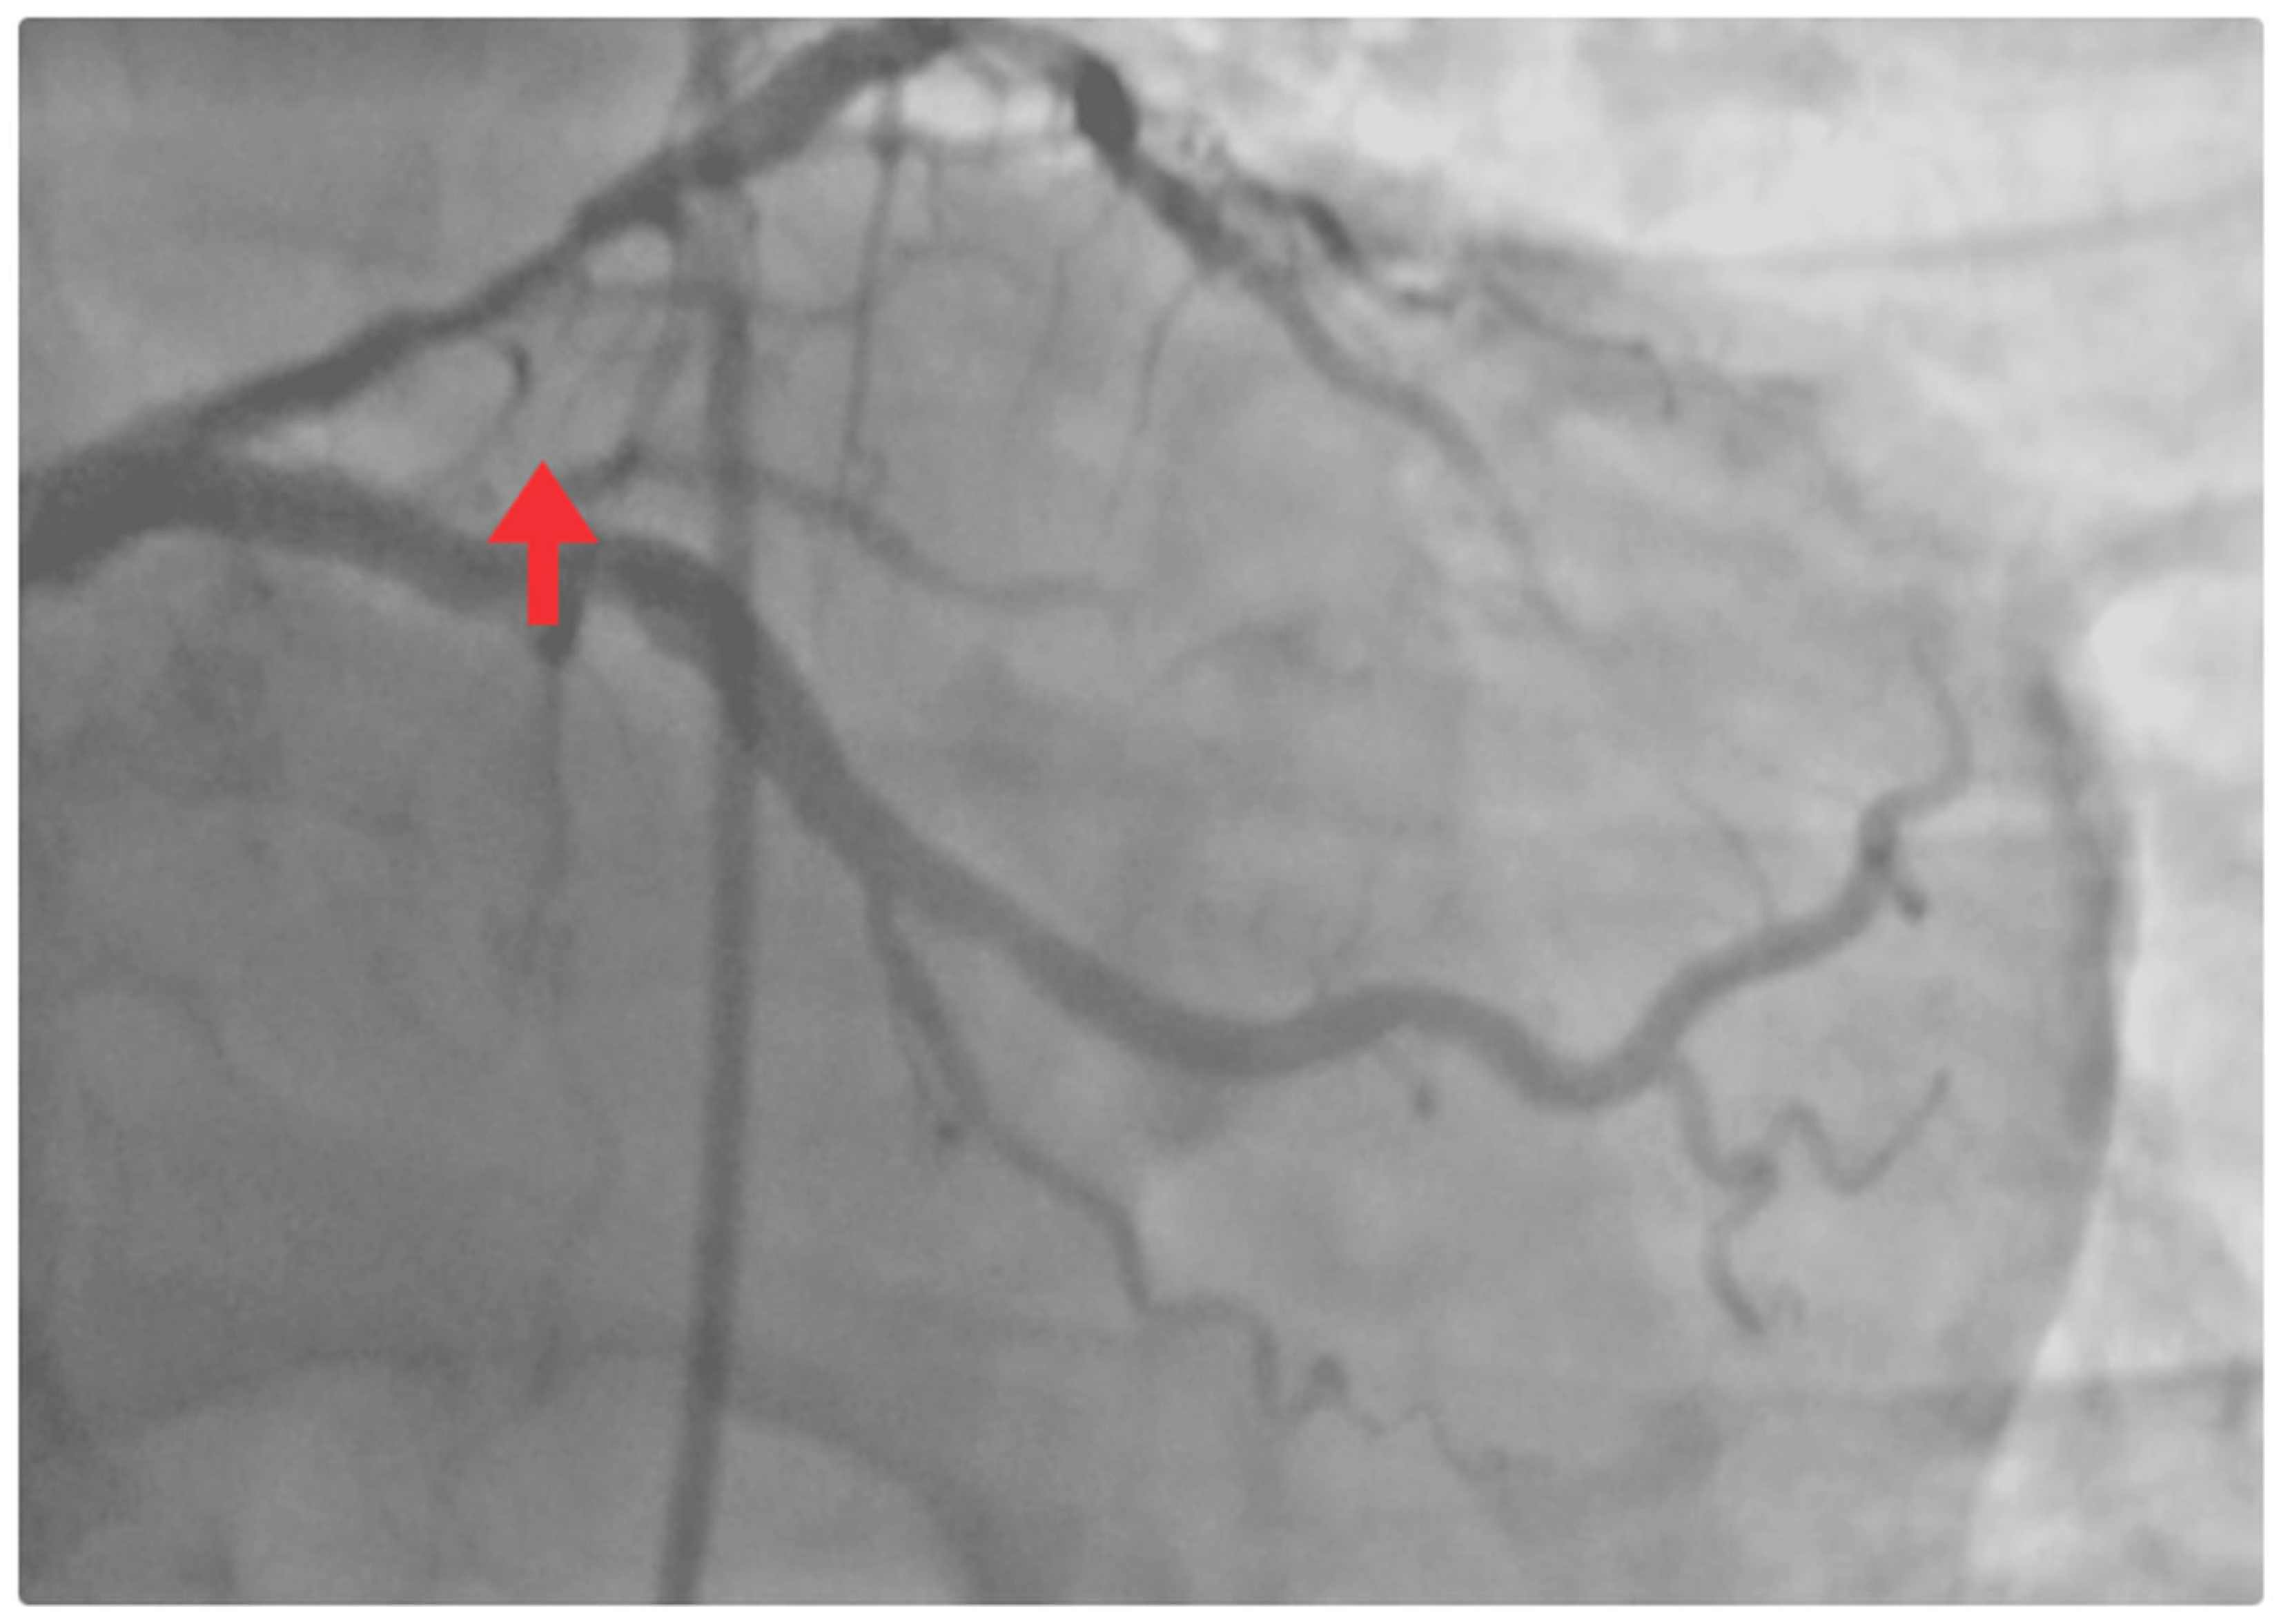

| 8 May | Mild retrosternal chest pain, absence of dyspnea, and improved ventilatory mechanics. | - | - | Coronary angiography: critical proximal LAD stenosis (>90%). Chronic atherosclerotic disease in the circumflex artery, without significant obstructive lesions. Percutaneous coronary intervention (PCI): angioplasty + drug-eluting stenting in the proximal LAD (TIMI 3 flow). |